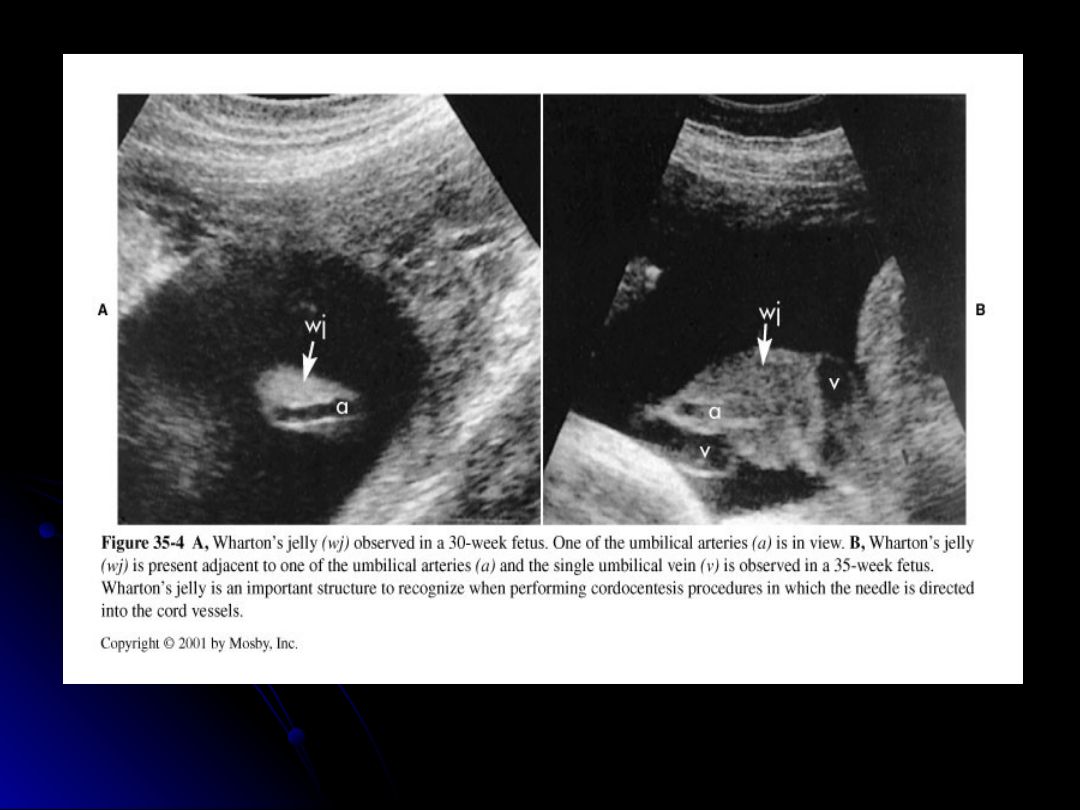

Based on the sonographic appearance, what are two key features to assess in the umbilical cord during gestation?

Cord twist and number of umbilical arteries